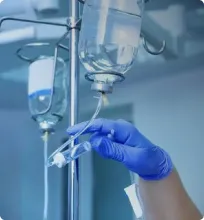

Зависимость считается хроническим заболеванием, но медицинская помощь позволяет достичь длительной ремиссии и вернуть свободу выбора. Комплексная программа, составленная с учётом типа аддикции и индивидуальных особенностей, поможет вам или вашему близкому снизить тягу, восстановить эмоциональное равновесие и вернуться к полноценной жизни без навязчивых потребностей, опираясь на доказательные методы работы.

Лечение проходит в условиях полной конфиденциальности: данные не передаются третьим лицам, не отражаются в официальных реестрах и защищены внутренними протоколами. Наши врачи в клинике «Наше здоровье» в городе Сергач обеспечат безопасное пространство, где вы или ваш близкий сможете открыто обсудить проблему и получить профессиональную поддержку, которая позволит начать путь к восстановлению без страха осуждения или социальных последствий.

Сроки восстановления индивидуальны и зависят от типа зависимости, стажа, мотивации и готовности к изменениям, но первые положительные сдвиги в самочувствии и поведении заметны уже через несколько недель регулярной работы со специалистами. Медицинская помощь позволит стабилизировать состояние, снизить интенсивность тяги и вернуть эмоциональное равновесие, чтобы вы или ваш близкий смогли постепенно и безопасно вернуться к привычной социальной жизни.

Первый приём посвящён детальной диагностике и доверительной беседе: врач внимательно выслушает, оценит ситуацию, объяснит возможные варианты помощи и дальнейшие шаги без каких-либо обязательств. Такой бережный формат позволит вам или вашему близкому получить чёткое понимание процесса лечения, снизить естественную тревогу перед началом терапии и принять взвешенное, осознанное решение о продолжении работы со специалистами.

Современные клинические протоколы позволяют эффективно работать с алкогольной, наркотической, пищевой, игровой, компьютерной и другими видами зависимостей, поскольку механизмы формирования навязчивой тяги имеют общие биохимические и психологические черты. Наши врачи в клинике «Наше здоровье» в городе Сергач подберут методику с учётом типа аддикции и особенностей пациента, чтобы медицинская помощь позволила вам или вашему близкому снизить навязчивые потребности, восстановить самоконтроль и вернуться к безопасному, осознанному поведению.